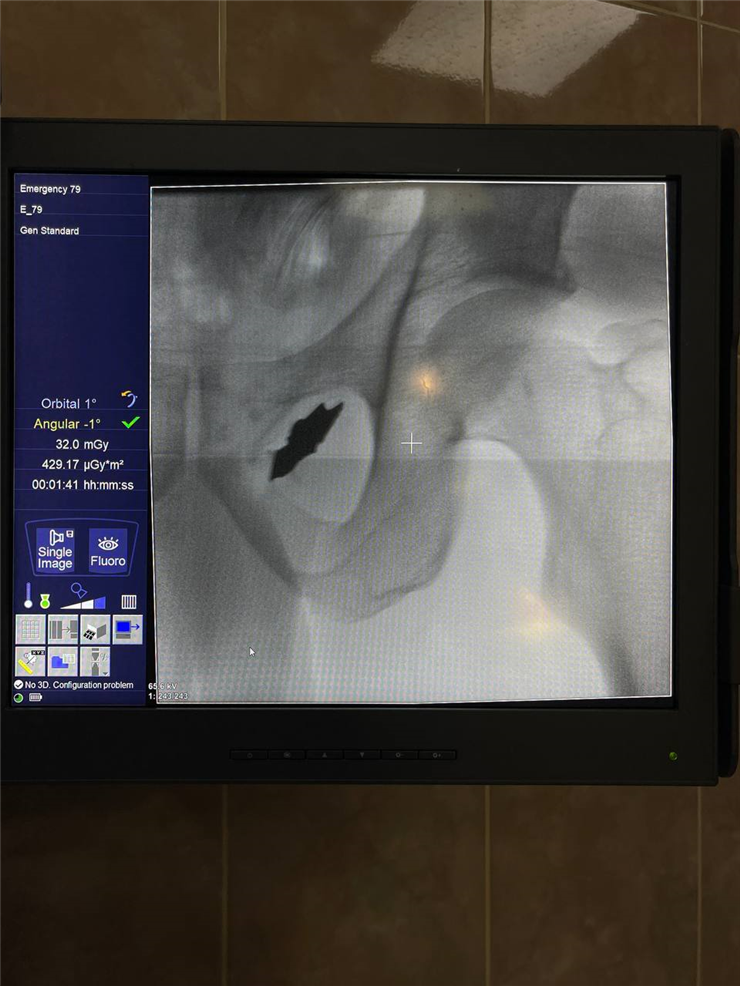

Ірина дуже зраділа, що змогла знайти лікаря, який знав що робити у подібному кейсі. Дівчині видалили небезпечні конкременти мініінвазивно, виконали лапароскопічну операцію Фрея (поздовжню панкреатоєюностомію на виключеній петлі за Roux з висіченням тканин голівки підшлункової залози, видаленням конкрементів, санацією панкреатичних проток), забезпечивши гарний косметичний ефект та швидке відновлення після втручання.